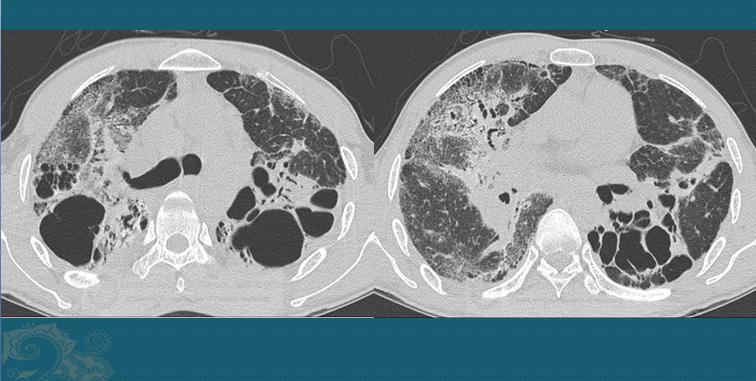

分为肺泡结节病、肉芽肿结节及肺纤维化。可以表现为边缘模糊的斑片影或者磨玻璃影、网格状影(如下图),其内可见含气支气管,两肺上叶多见;或者呈形状规则的小结节(多数大小2mm-1cm),多沿支气管血管束和小叶间隔、叶间裂、胸膜下的淋巴管网分布,以肺野中带及胸膜下较为明显,如上图第一位小伙子,不要误诊为转移瘤。

这是一种良性疾病,发展缓慢,很多病人会在1-2年内症状和影像学改变都自行消退(自愈),但大于20-25%的病人会进展为肺纤维化,肺内出现纤维灶、蜂窝状影、牵拉性支气管扩张等,或者继发细菌感染。